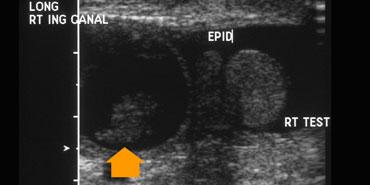

Ở trẻ rất nhỏ, việc khám tinh hoàn có thể gặp khó khăn do tinh hoàn rất nhỏ và di động.

Tinh hoàn trước dậy thì có thể tích khoảng 1-2 cc, trong khi tinh hoàn sau dậy thì có thể tích khoảng 30cc.

Theo độ tuổi, tinh hoàn tăng dần độ hồi âm, do đó ở trẻ rất nhỏ, tinh hoàn nhỏ có thể khó phân biệt với mô mỡ xung quanh, đặc biệt khi tinh hoàn co rút vào ống bẹn (hình).

Khi bắt đầu thăm khám, bạn có thể đặt ngón tay lên ống bẹn để tinh hoàn không thể di chuyển xung quanh.

Siêu âm Doppler màu có độ nhạy hạn chế trong việc phát hiện lưu lượng máu ở bệnh nhân nhi có thể tích tinh hoàn nhỏ hơn 1cc.

Ở bên trái là hai trường hợp nữa.

Ở ngoài cùng bên trái là một trẻ 10 tháng tuổi bị xoắn tinh hoàn.

Có nhiều lưu lượng máu trong các mô xung quanh tinh hoàn hơn so với trong tinh hoàn, điều này là bất thường, trừ khi trẻ bị viêm mô tế bào.

Ca bên cạnh là một trẻ lớn hơn.

Siêu âm thang xám cho thấy tinh hoàn bất thường.

Vì vậy đây có thể là xoắn tinh hoàn hoặc viêm tinh hoàn, nhưng sự vắng mặt của dòng chảy cho chúng ta biết rằng đây chắc chắn là xoắn tinh hoàn.